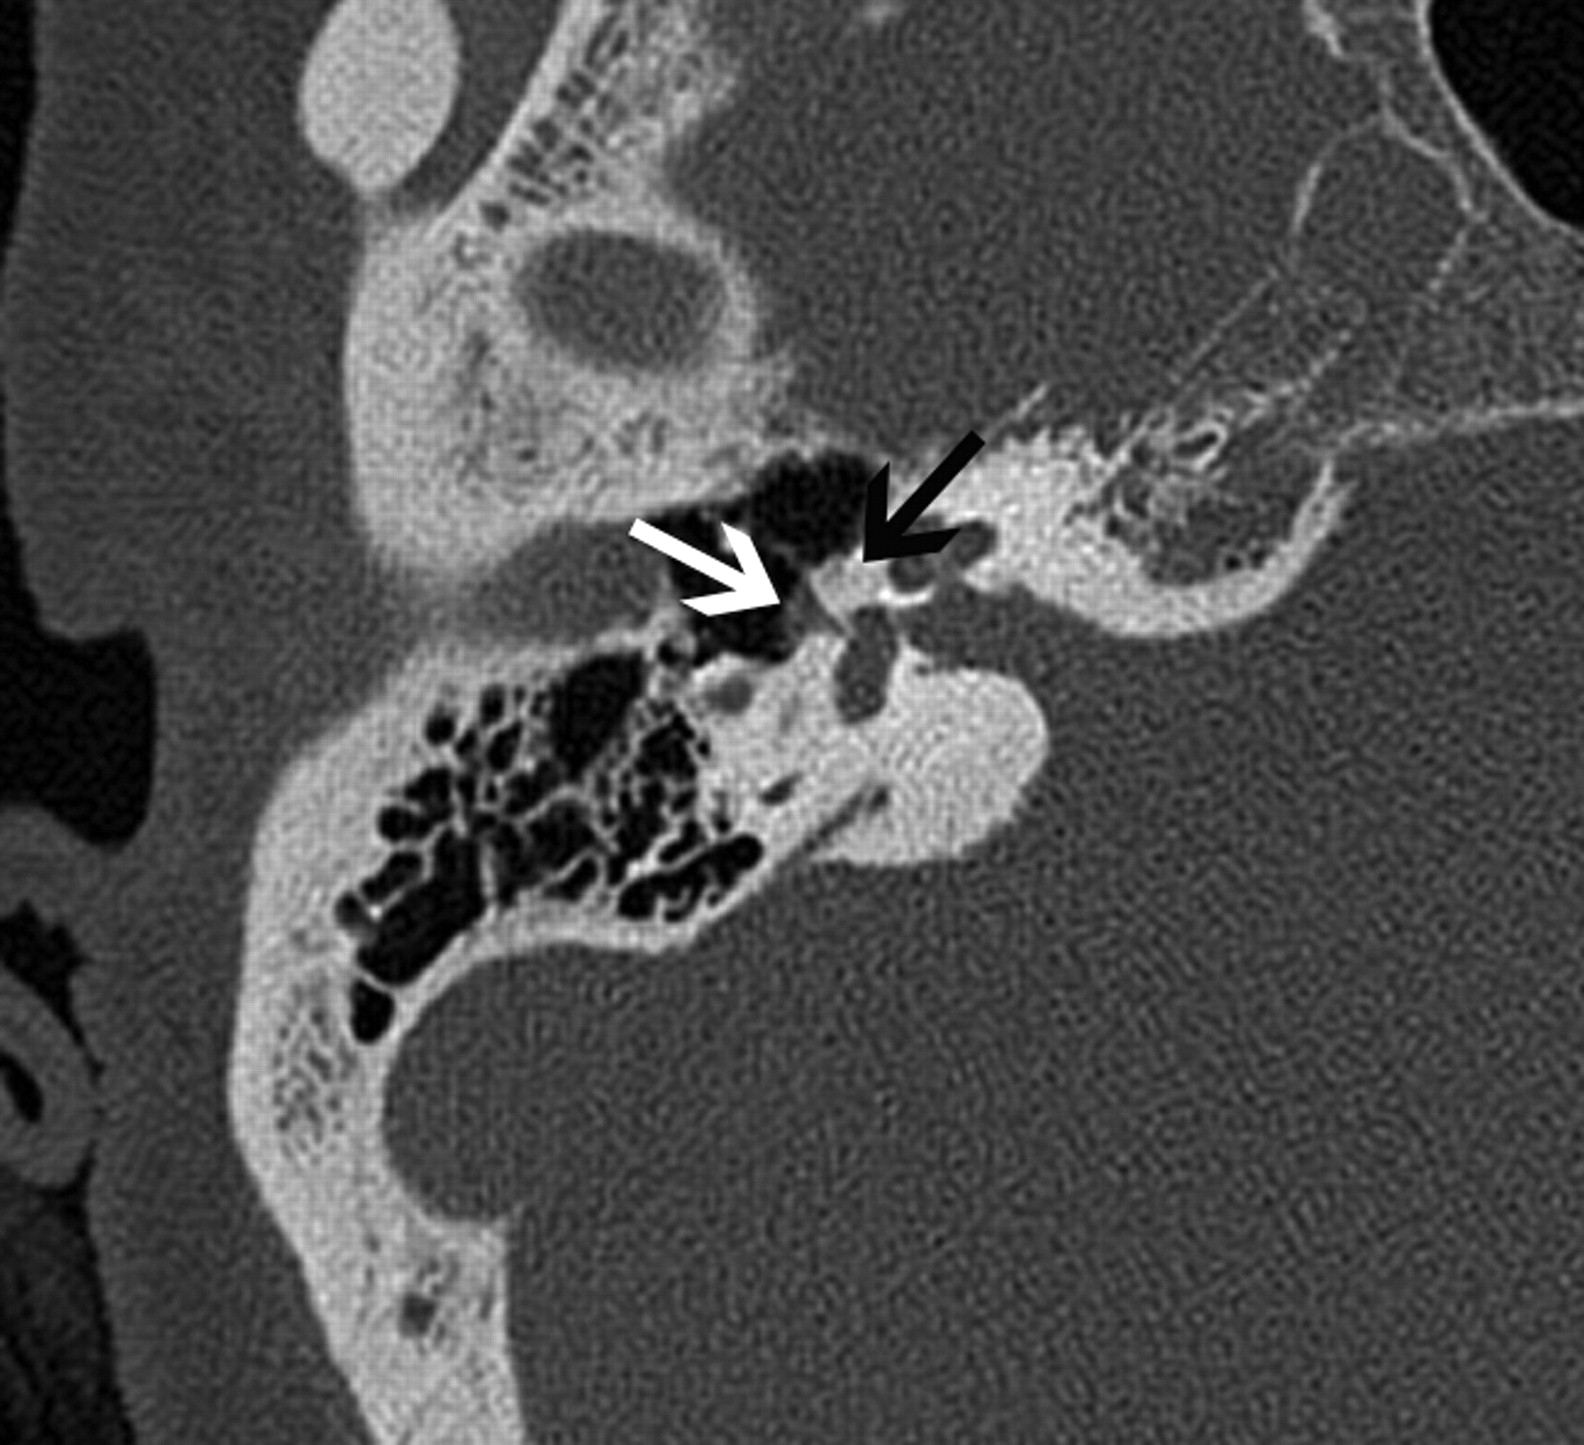

Absence of the foramen spinosum and enlargement of the proximal tympanic facial nerve canal may indicate the presence of a PSA (Fig 8A–C). The stapedial artery is normally present in the fetus but undergoes regression before birth. It arises from a normal or aberrant ICA (approximately 30% of all aberrant ICAs are associated with a PSA). The PSA typically runs through the obturator foramen (the space between the crura of the stapes) and across the promontory in the middle ear, where it can sometimes be identified. The PSA then runs along the tympanic portion of the facial nerve canal near the geniculate fossa, finally exiting the facial nerve canal to enter the middle cranial fossa to become the middle meningeal artery.

A 30-year-old man with PSA. A, Axial CT image demonstrates absence of the foramen spinosum bilaterally (black arrows). B, Coronal CT image in the same patient shows enlargement of the tympanic part of the facial nerve canal, another indirect imaging sign of PSA. C, Lateral DSA image of the internal carotid injection shows the PSA arising from the ICA (arrows).

When the stapedial artery persists beyond the fetal period, the middle meningeal artery does not develop from the internal maxillary artery and the foramen spinosum remains undeveloped. The absence of the foramen spinosum is an important CT finding that should alert the radiologist to a possible PSA (Fig 8A). However, these findings do need to be interpreted cautiously because the foramen spinosum may be absent in ≤3% of all skull base CT studies.35 The presence of additional signs such as a subtle enlargement of the tympanic segment of the ipsilateral facial nerve canal on coronal CT images, just inferior to the lateral semicircular canal, may raise the index of suspicion (Fig 8B), and DSA can be used for confirmation (Fig 8C). Most patients with a PSA remain asymptomatic and only rarely present with pulsatile tinnitus. The physical examination in some patients may show a red retrotympanic mass, which may provide useful clinical correlation for the imaging findings.